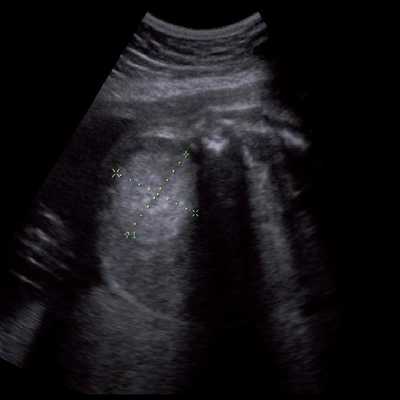

Под диафрагмой справа визуализировалось гиперэхогенное опухолевидное образование несколько неоднородной солидной структуры, с четкими ровными контурами, размером 50x38x35 мм. К нижнему полюсу данного образования прилежала правая почка, имеющая нормальные размеры, форму и структуру. Нижняя полая вена была смещена кпереди и влево. Обращала на себя внимание выраженная гепатомегалия, причем структура печени не была однородной. Она содержала множественные гиперэхогенные включения размерами до 17 мм, окруженные тонким гипоэхогенным периферическим ободком. Цветовое допплеровское картирование(ЦДК) демонстрировало интенсивную периферическую васкуляризацию опухоли (рис. 1-3).

Рис. 2. Кровоток в нейробластоме плода. Цветовое допплеровское картирование. Отчетливо виден питающий сосуд, огибающий образование по его периферии. К нижнему полюсу образования прилежит интактная почка плода.

Кровоизлияние в надпочечники, как правило, выглядит эхогенным или неоднородной структуры образованием, иногда может быть полностью анэхогенным и характеризуется изменением ультразвуковой картины при динамическом исследовании, постепенно превращаясь в анэхогенное кистозное образование, в котором с течением времени отмечается утолщение его стенки [13] и образуются кальцификаты. Энергетический допплер демонстрирует полную аваскулярность такого образования. В нашем случае образование имело повышенную эхогенность, несколько неоднородную структуру. При ЦДК в опухоли регистрировался преимущественно периферический кровоток.